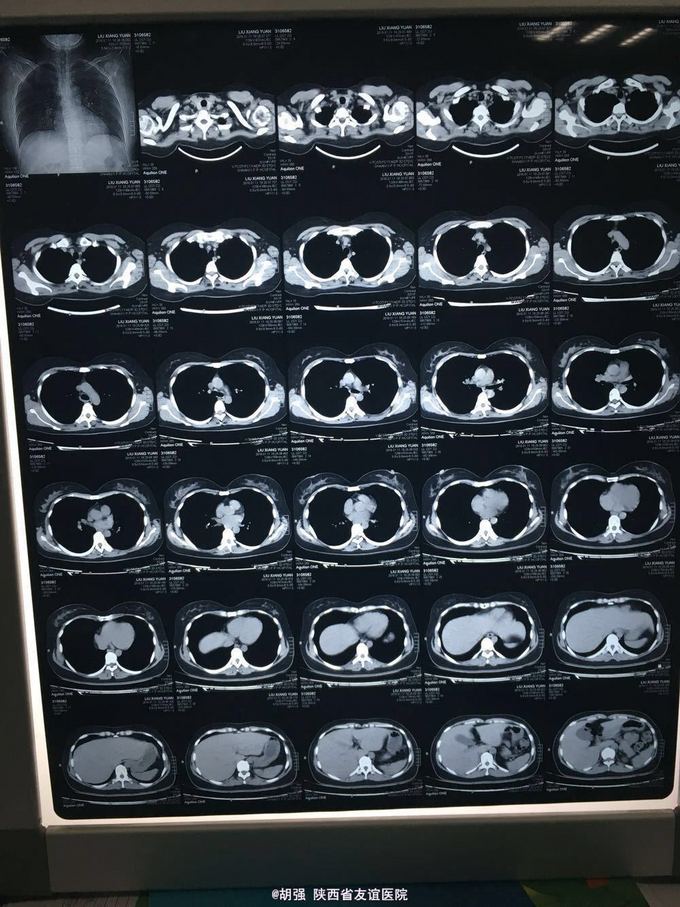

32岁女性患者,咳嗽、咳痰2周余 患者于两周前不明诱因出现咳嗽、咳痰,无胸痛咯血,无胸闷气短,无发热、寒战,自己服用头孢克肟1.0 2次/日及复方甘草合剂10ml3次/日治疗1周,效果不佳,遂来我院。 既往体检。

查体:两肺呼吸音粗糙,未闻及干湿性啰音及胸膜摩擦音。余查体无明显异常。 入院后查胸部CT无明显异常。血常规、肝肾功、血沉、结核抗体、心电图大致正常。T-sport试验及PPD试验 阴性。支气管镜检查:右肺中叶可见大量脓痰,吸痰送检。痰培养回报:肺炎链球菌。